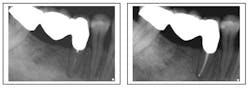

Missed canal anatomy cases ...

Missed MB2 canal

Missed third canal in upper first premolar

Separated instrument with incomplete fill and debridement